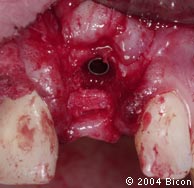

42. | 带着聚乙烯愈合帽就位的种植体。 |

43. | 插入肩台深度量尺,确定肩台的高度为3.5mm可以恰好位于牙龈顶下。 |

44. | 使用指压的力量将4.0mm×3.5mm的隐匿肩式基台插入种植体的内径。 |